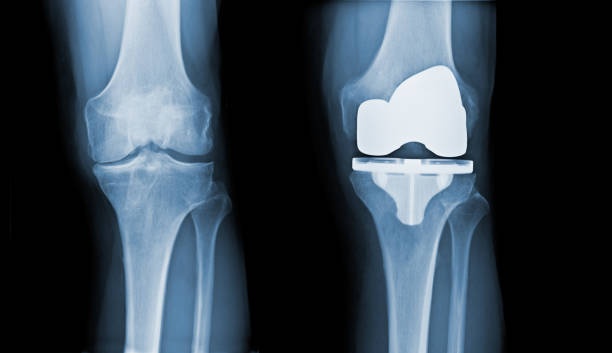

Total knee replacement surgery, also known as total knee arthroplasty or TKR/TKA, is a surgical marvel that involves replacing a damaged or deteriorated knee joint with an artificial joint or prosthesis. Typically, this surgery is recommended for individuals grappling with debilitating knee pain due to conditions such as osteoarthritis, rheumatoid arthritis, or traumatic injuries to the knee joint. So, how do you know if a knee replacement is the right course of action for you? Orthopedic surgeons often suggest that when the time is right for a replacement, you'll instinctively know it. Before jumping to the surgical option, most orthopedists advocate exploring physical therapy as an initial measure to see if surgery can be avoided. If a total knee replacement is still the recommended course of action even after pursuing physical therapy, take comfort in the knowledge that your dedication to PT has not been in vain. Research reveals that individuals who undergo pre-surgery physical therapy tend to achieve more favorable post-operative results!

- The damaged portions of the thigh bone (femur) and shinbone (tibia) are removed and these bone surfaces are then reshaped to accommodate the artificial components of the knee prosthesis.

- The artificial knee joint, consisting of metal and plastic components, is securely implanted. The femoral component replaces the end of the thigh bone, the tibial component replaces the top of the shinbone, and a plastic spacer is inserted between them to allow smooth movement.

- If needed, the undersurface of the kneecap (patella) may be resurfaced with a plastic component.